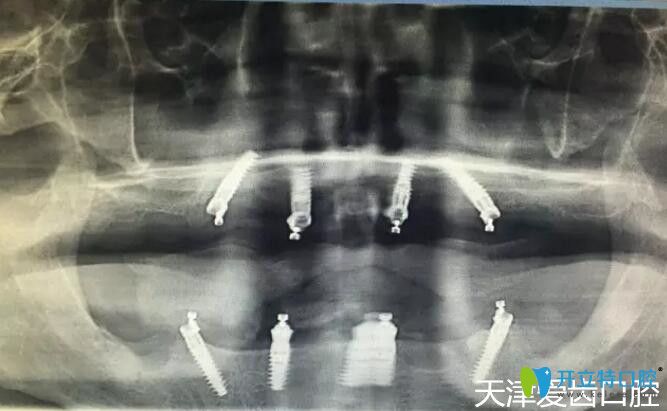

我在天津愛齒口腔做allon4全口種植牙術(shù)后CT片

郭平川醫(yī)生給我做的ALL-ON-4全口種植牙手術(shù),從拔牙到裝上臨時(shí)牙冠,僅用了2個(gè)多小時(shí),從手術(shù)室出來(lái)我就擁有了一口嶄新的“牙齒”,而且當(dāng)天下午回家就能吃東西啦!